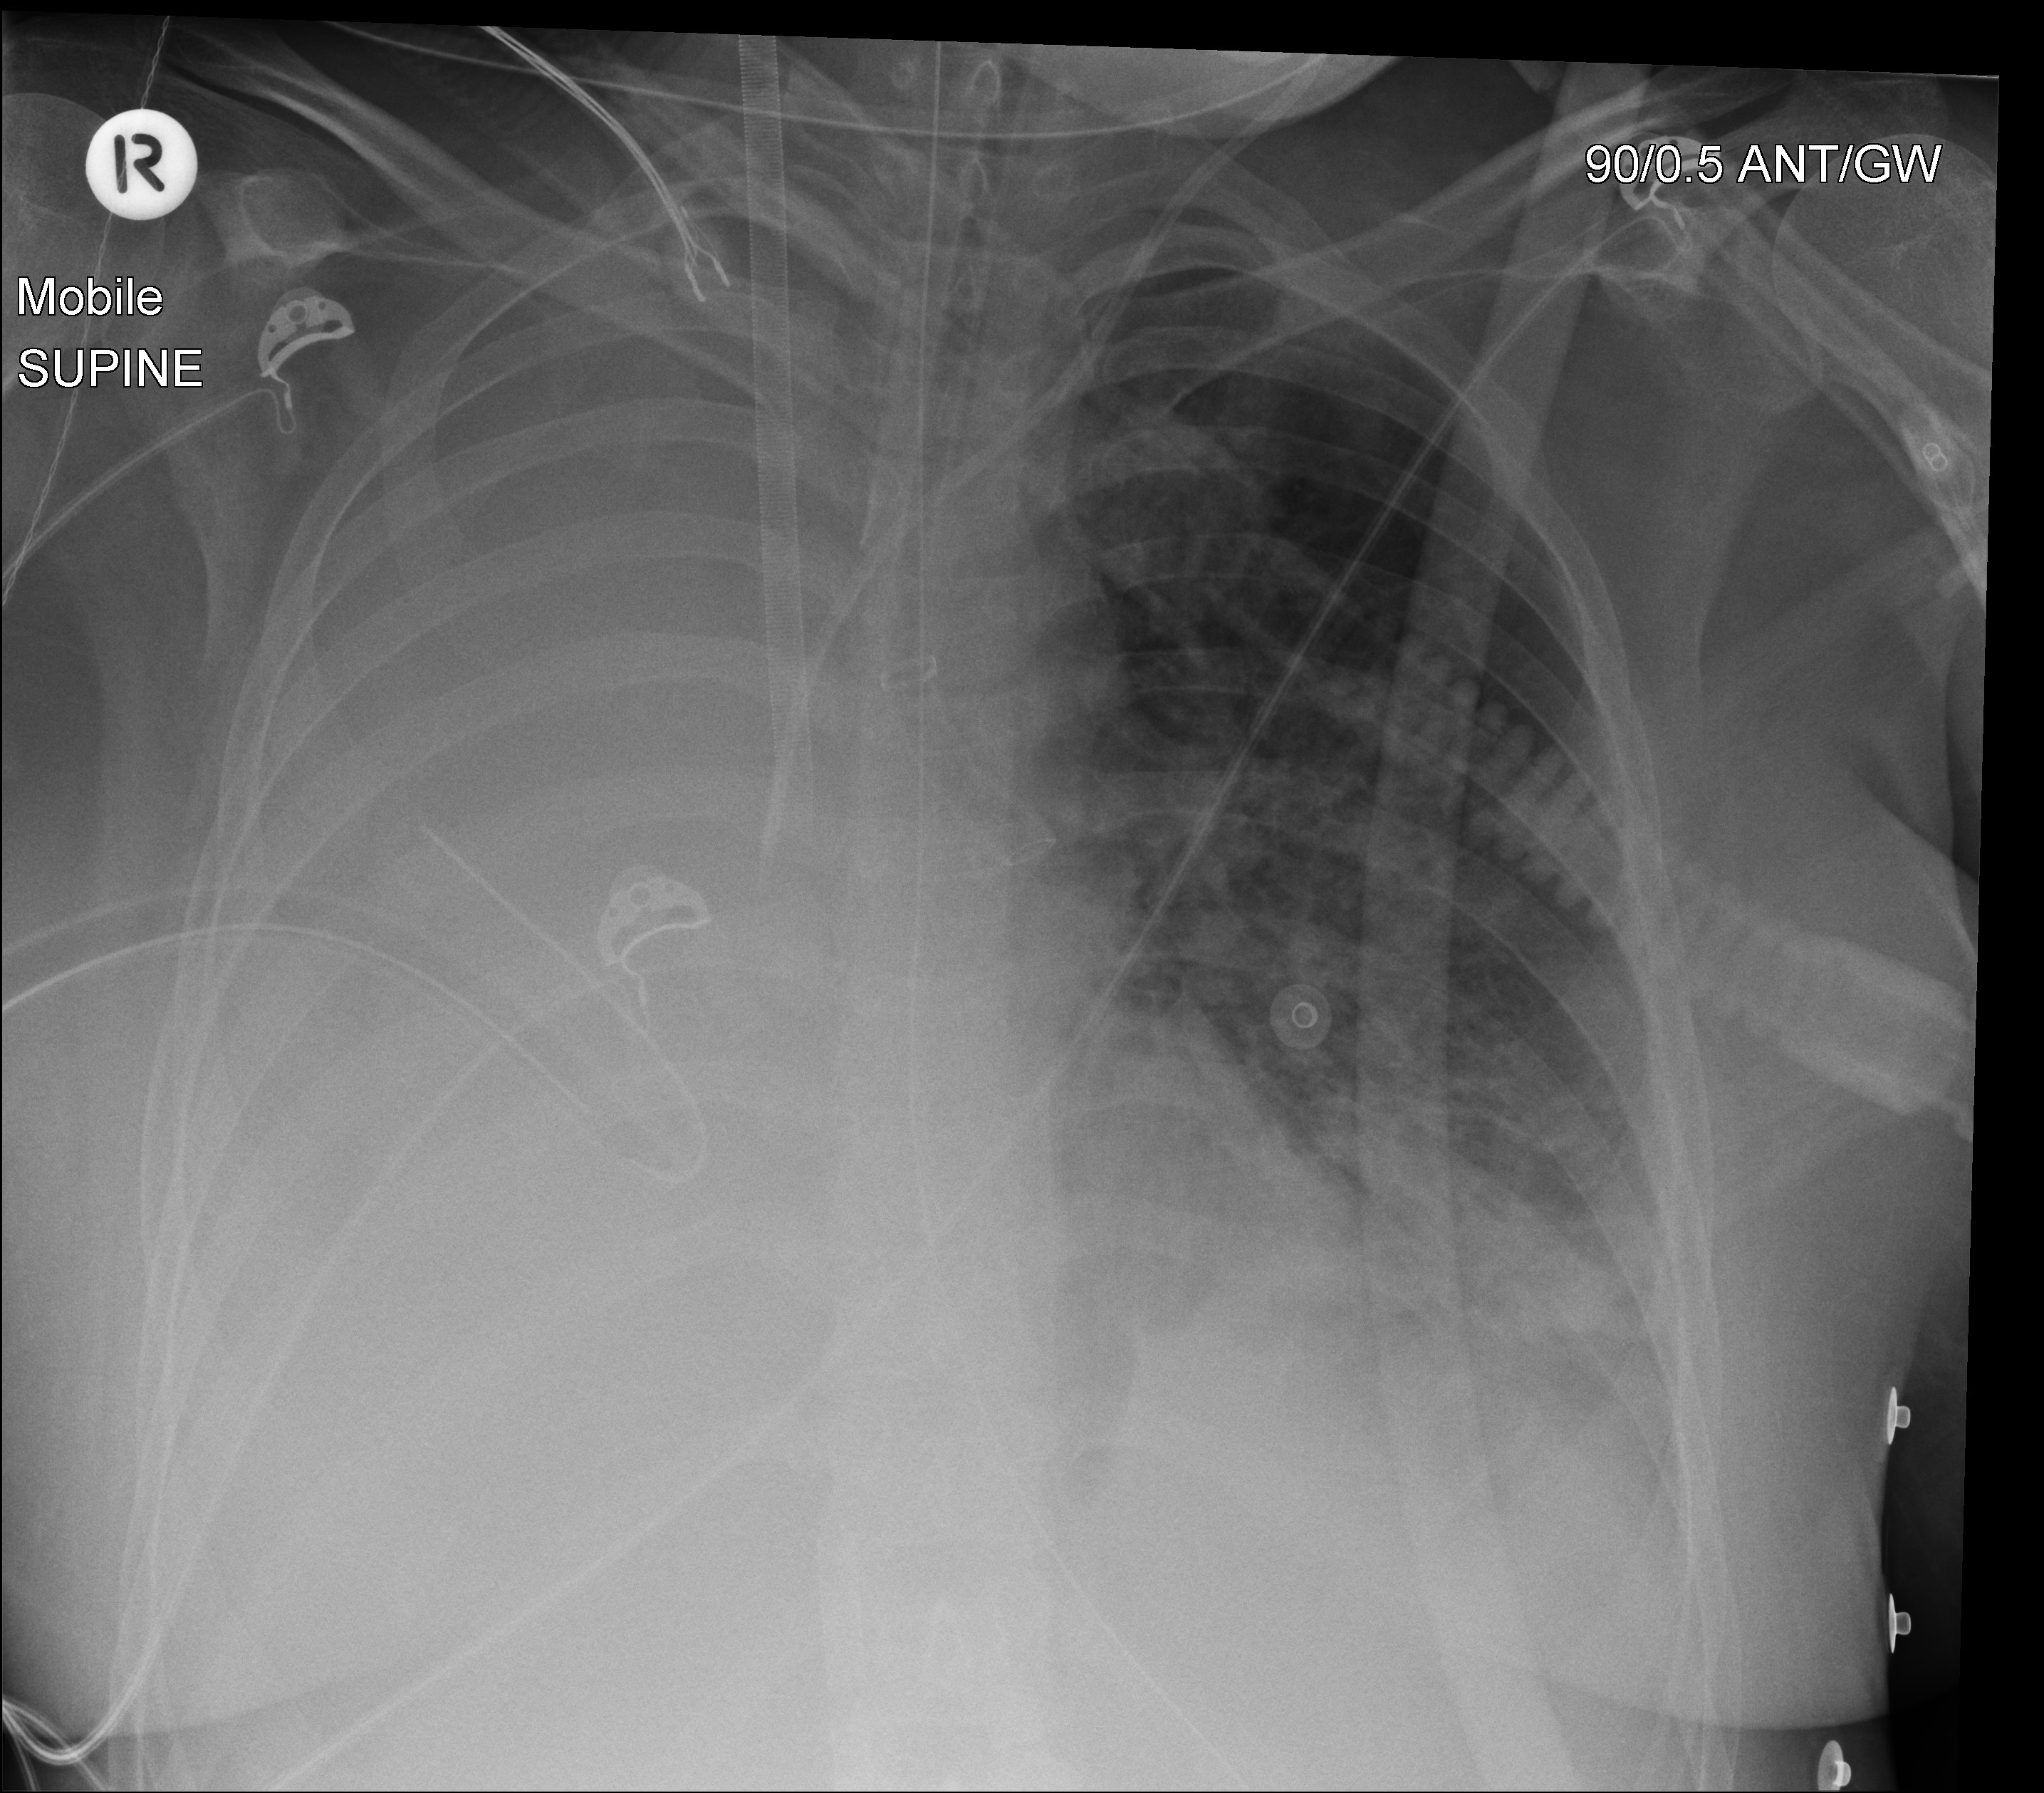

Chest xrays. The arrow denotes the presence of air bubbles in the Big Air Bubble In Chest Asthma one of the major symptoms of asthma, besides. This can lead to an inflated feeling and chest tightness or shortness of. Here are nine of the most common causes behind the bubbling feeling in your chest: Pneumomediastinum occurs when air or another gas becomes trapped in the center of the chest, in a cavity known as the mediastinum. As. Big Air Bubble In Chest.